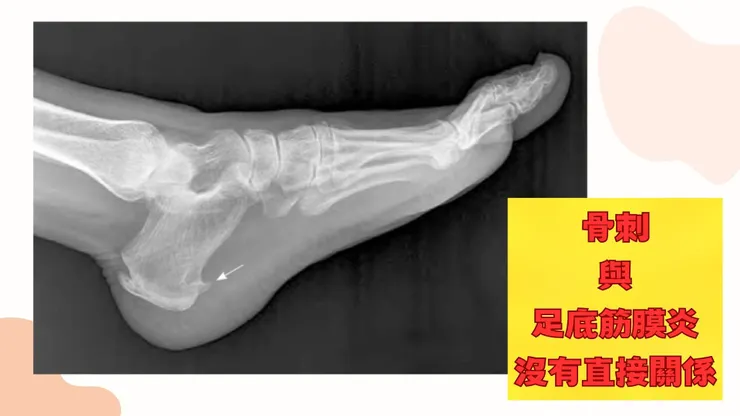

常見問題1:老師我的足跟長骨刺,是不是那個骨刺刺到我的筋發炎呢?